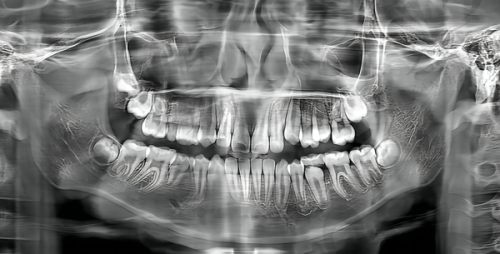

作为德系齿科连锁品牌,南昌德亚口腔门诊部具有进口设备和德国管理服务。在设备方面,精良的口腔治疗工具和设备能够为治疗提供更精细的支持。例如,数字化口腔设备可以更清晰地显示牙齿的内部结构,帮助医生制定更正确的治疗方案。